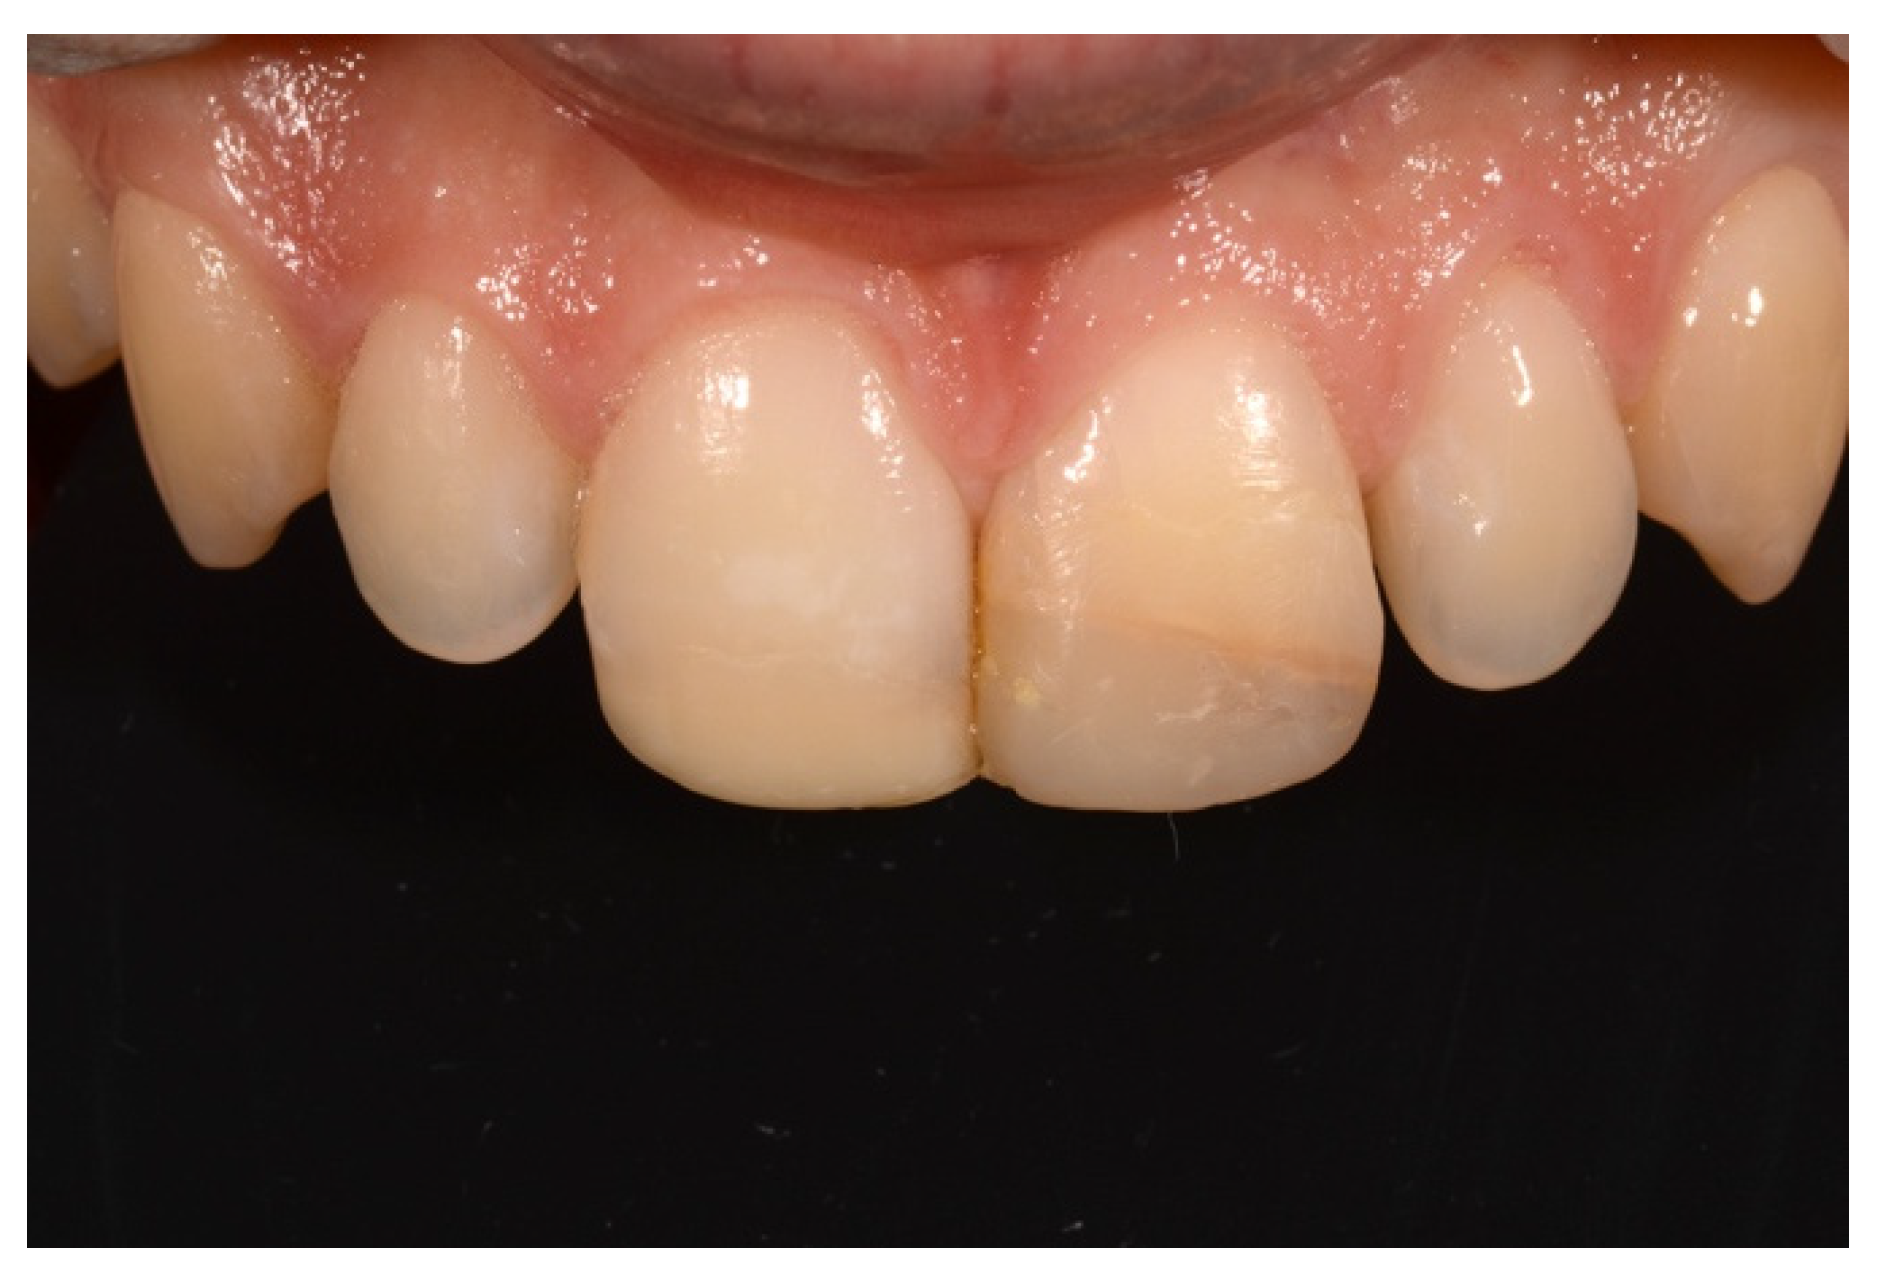

2. Case Presentation

- Molding palatal wall and incisal margin;

- Building interproximal walls with matrices;

- Layering free-hand buccal surface.